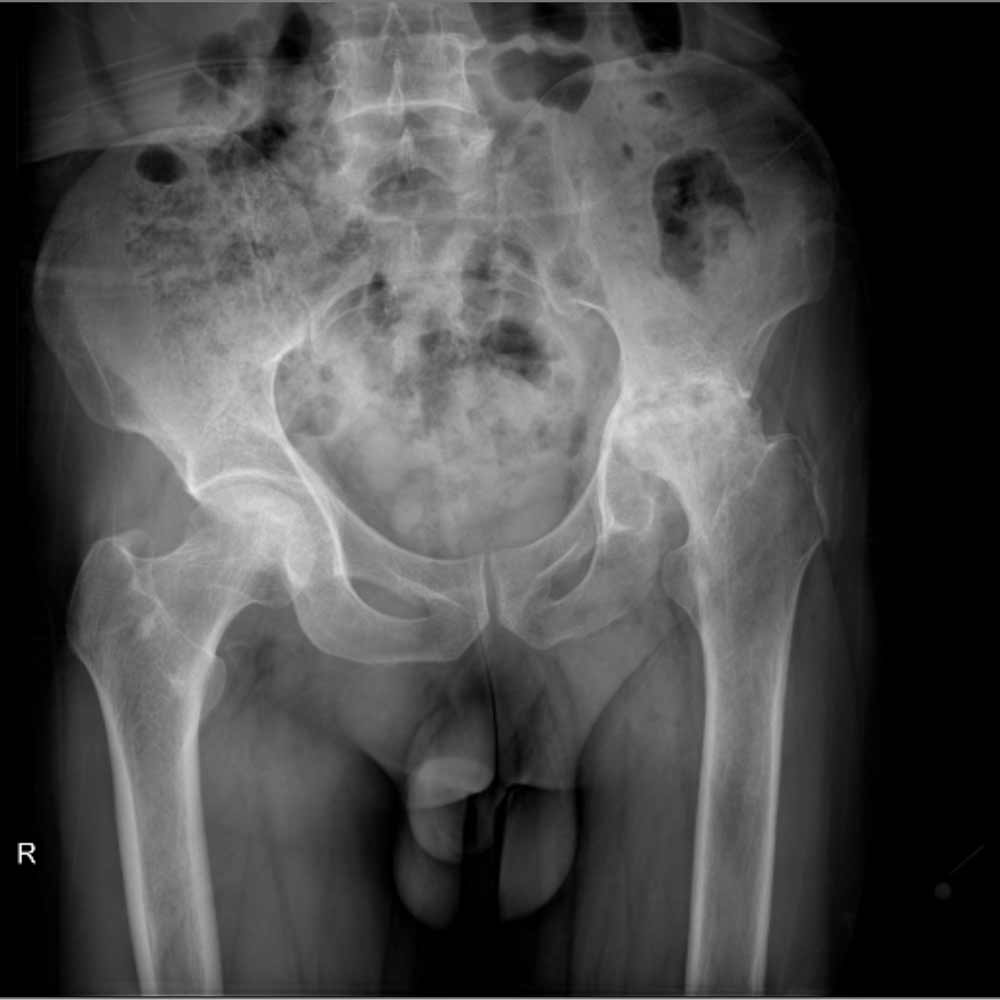

در نهایت، روش های تصویر برداری مثل رادیوگرافی به تشخیص بیماری کمک میکند. مهمترین روش تصویربرداری برای تشخیص ساییدگی لگن رادیوگرافی ساده است. تشخیص این بیماری نیاز به سی تی اسکن یا ام ار آی ندارد.

در تصویر رادیوگرافی از مفصل، چون غضروف نازک شده است فاصله مفصلی یا فاصله بین دو استخوانی که مفصل را تشکیل داده اند و در حد چند میلیمتر است کاهش پیدا میکند و در کناره های استخوان های تشکیل دهنده مفصل استخوان اضافی دیده میشود.

همچنین ممکن است کیست های استخوانی در بالای استابولوم یا در سر استخوان ران دیده شود.

در زیر تصاویری از عکس ساییدگی لگن در چند بیمار را میبینید. با کلیک بر روی هر کدام تصویر بزرگتری از آن را خواهید دید.